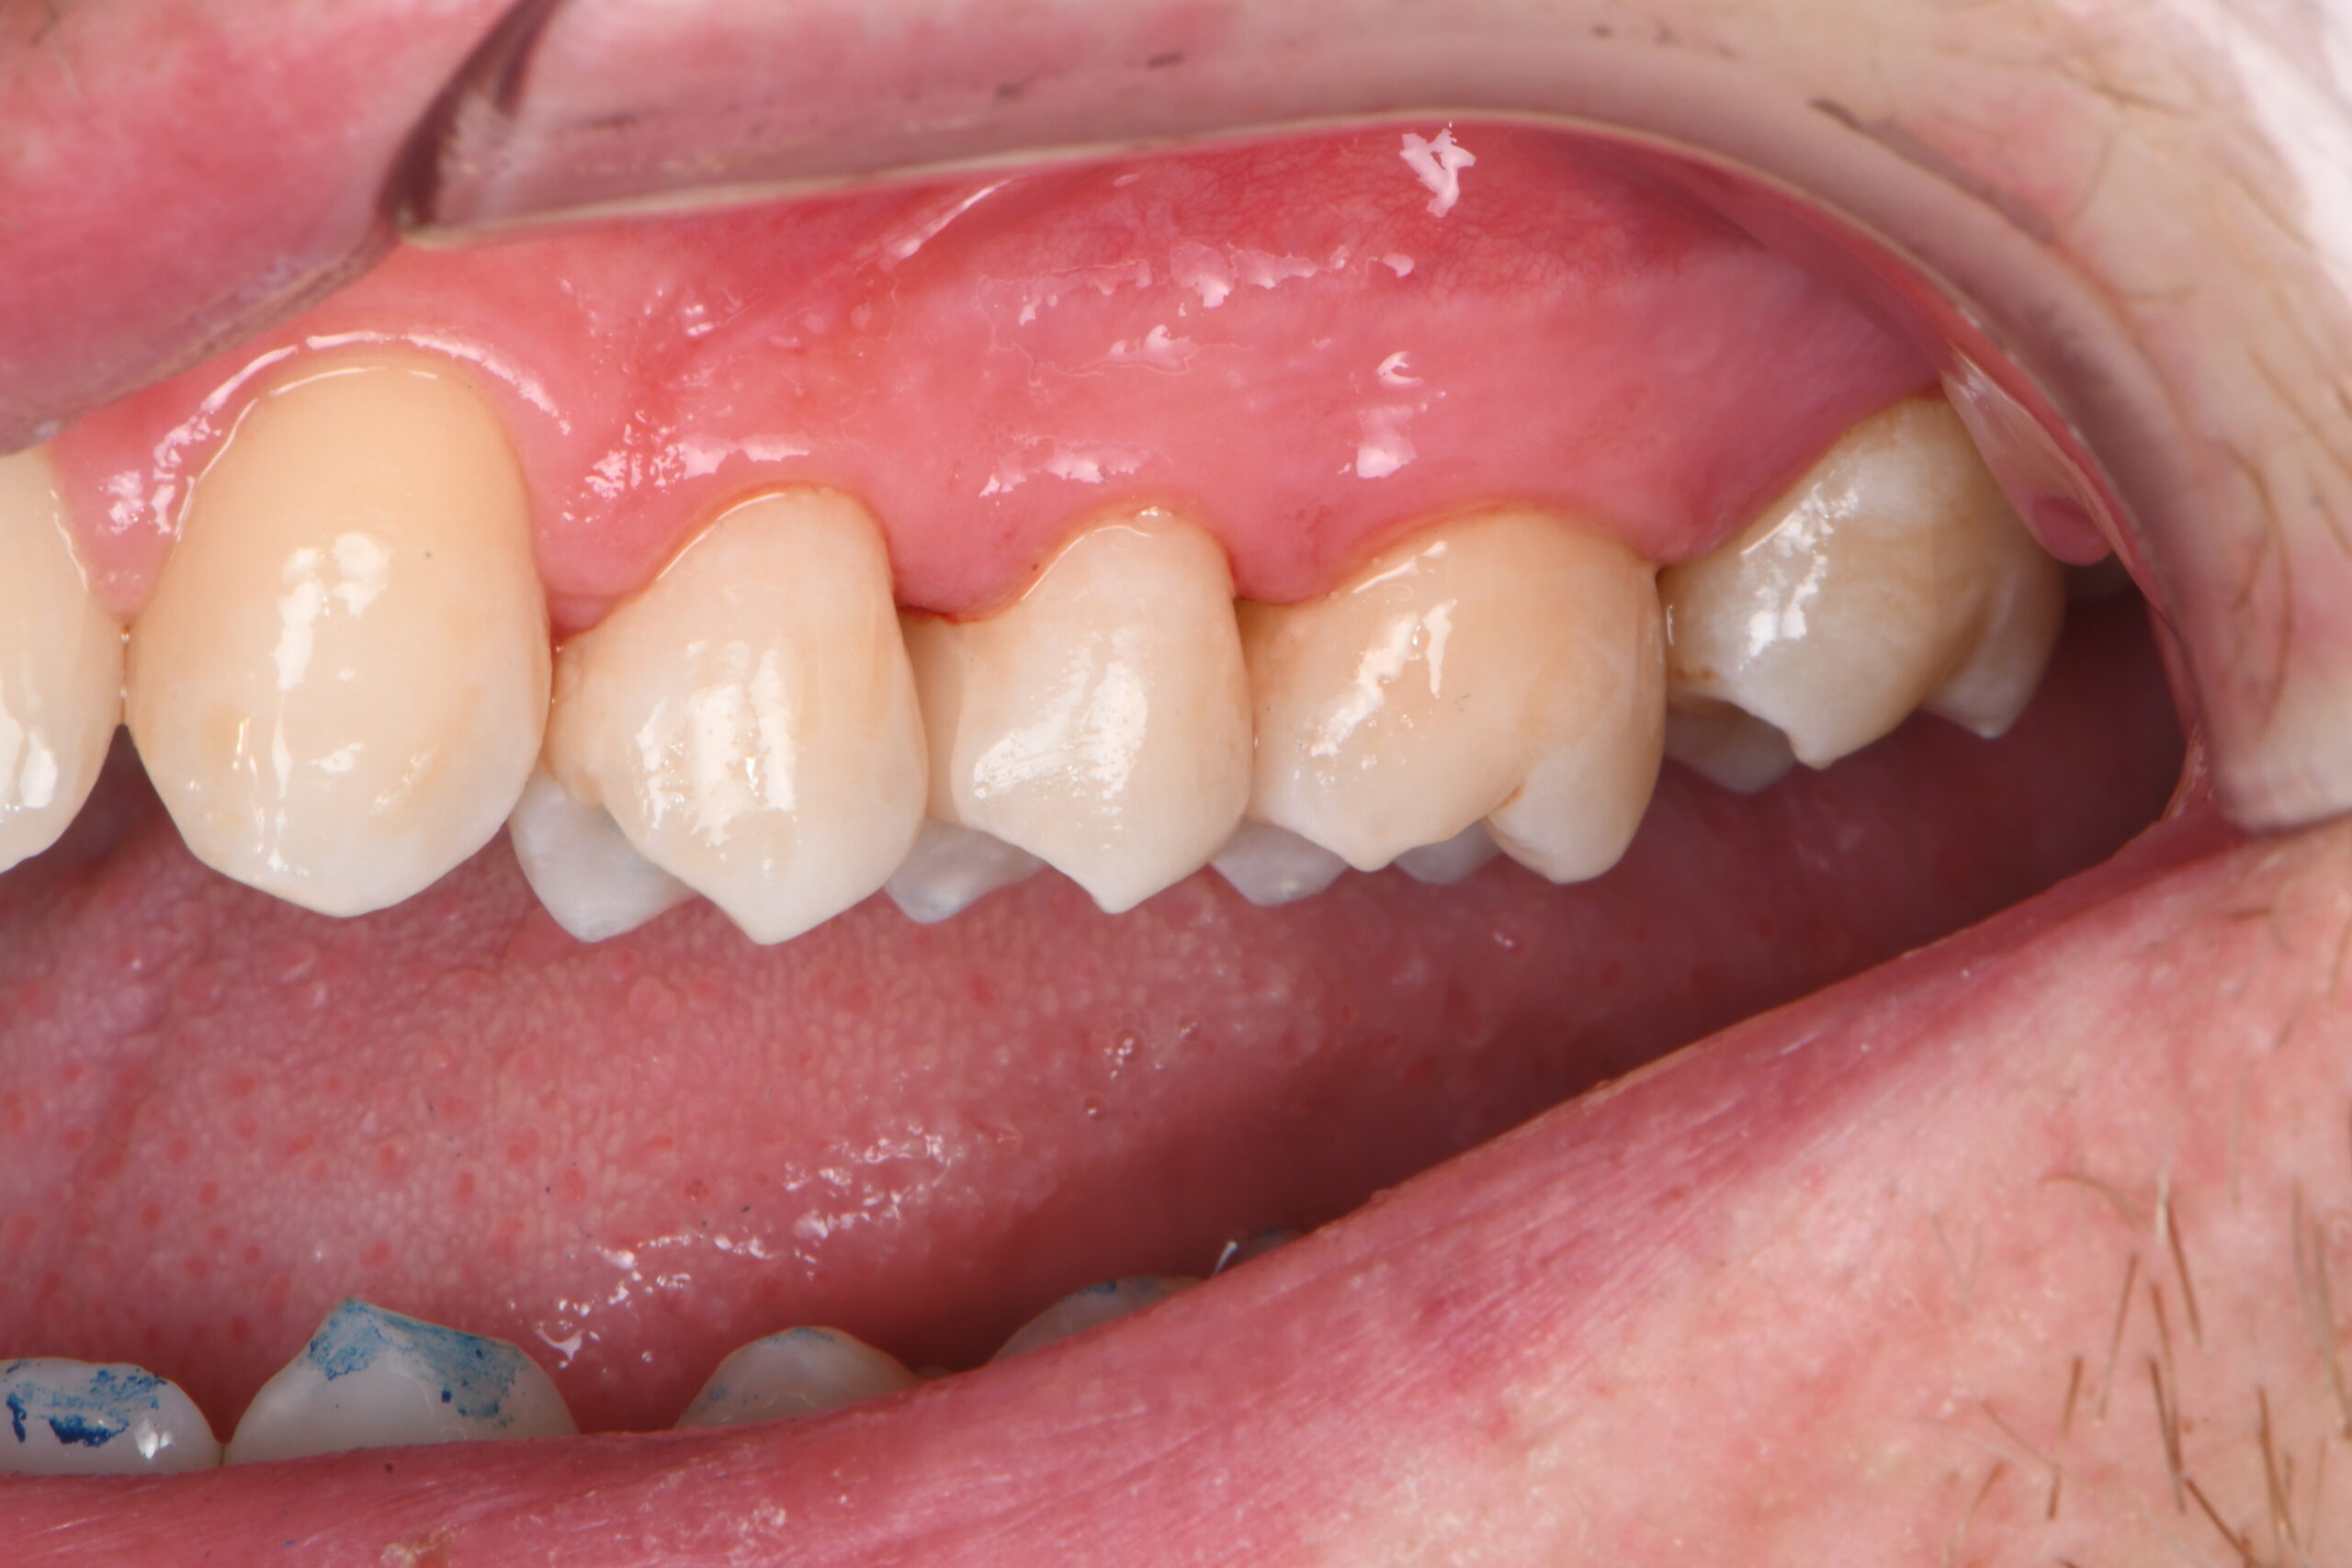

Close-up of lower molars and premolars with visible dental plaque and discoloration on some teeth

Pre-op vestibular view.

Close-up of upper teeth showing dental crowns and natural teeth with visible gums

Post-op vestibular view.